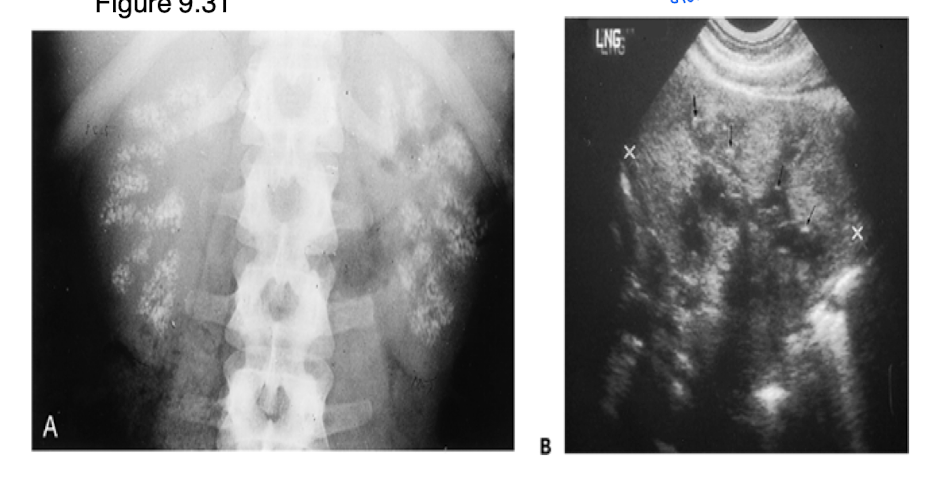

What is shown in this ultrasound of the urinary system?

normal renal ultrasound with the right image being the kidneys

What is nephrocalcinosis? How does it appear on film?

calcium deposits in renal tissue due to increased serum calcium

Uniform opacity, bilateral, and stone is clear, and precise